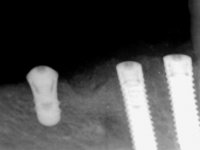

Realizada uma TAC, foi planificada a colocação de 6 implantes no maxilar superior. Foi decidida a colocação de dois implantes na zona dos incisivos centrais, dois implantes na zona dos caninos e dois na zona dos segundos pré-molares. A ausência de estrutura óssea na zona distal do primeiro quadrante implicava a realização de uma regeneração óssea no seio maxilar direito. A cirurgia foi realizada e após a colocação dos implantes foi feita a impressão para confeção de uma prótese provisória metalo-acrílica aparafusada para colocação em carga imediata no dia seguinte. O implante colocado na zona do seio maxilar direito não foi colocado em carga. Passados 6 meses foi realizada a impressão aos 6 implantes com técnica de moldeira aberta e foram confecionados os modelos de trabalho. Numa consulta seguinte foram montados os modelos de trabalho em articulador semi-ajustável utilizando o arco facial e a relação inter-maxilar obtida com a prótese provisória. Foi feita uma muralha de silicone sobre a ponte provisória com o objetivo de orientar o trabalho laboratorial. Realizada a infra estrutura metálica aparafusada esta foi provada em boca e finalmente após colocação de cerâmica o trabalho foi colocado definitivamente. Como passaram vários meses após a realização da primeira TAC foi feita uma segunda para planificar a colocação de implantes no 4º quadrante. Colocaram-se 3 implantes na mesma sessão em que foi feita a extração dos pilares da ponte. Estes implantes foram posteriormente reabilitados com uma ponte metalo-cerâmica aparafusada de três elementos.